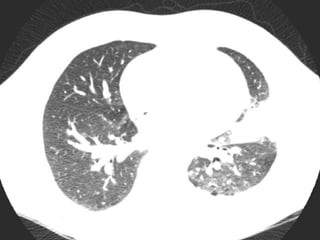

Imaging

CT chest with contrast

1. Scattered centrilobular nodules in the left lung with

associated ground glass.

2. Consolidation in the lingula, left hilar adenopathy

and a small left-sided pleural effusion.

3. No pulmonary embolism.